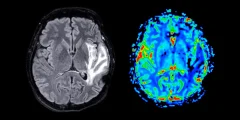

انقطاع الطمث وفقدان المادة الرمادية في الدماغ

تأثير الدهون غير المرئية على صحة الدماغ